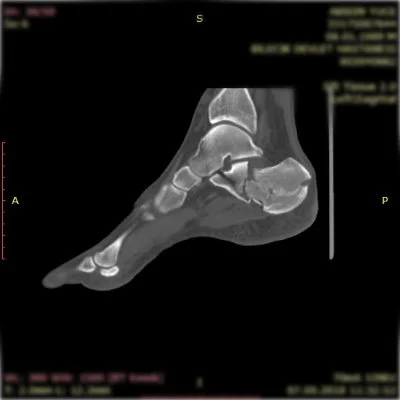

Görüntüleri büyütmek için resmin üstüne tıklayınız.